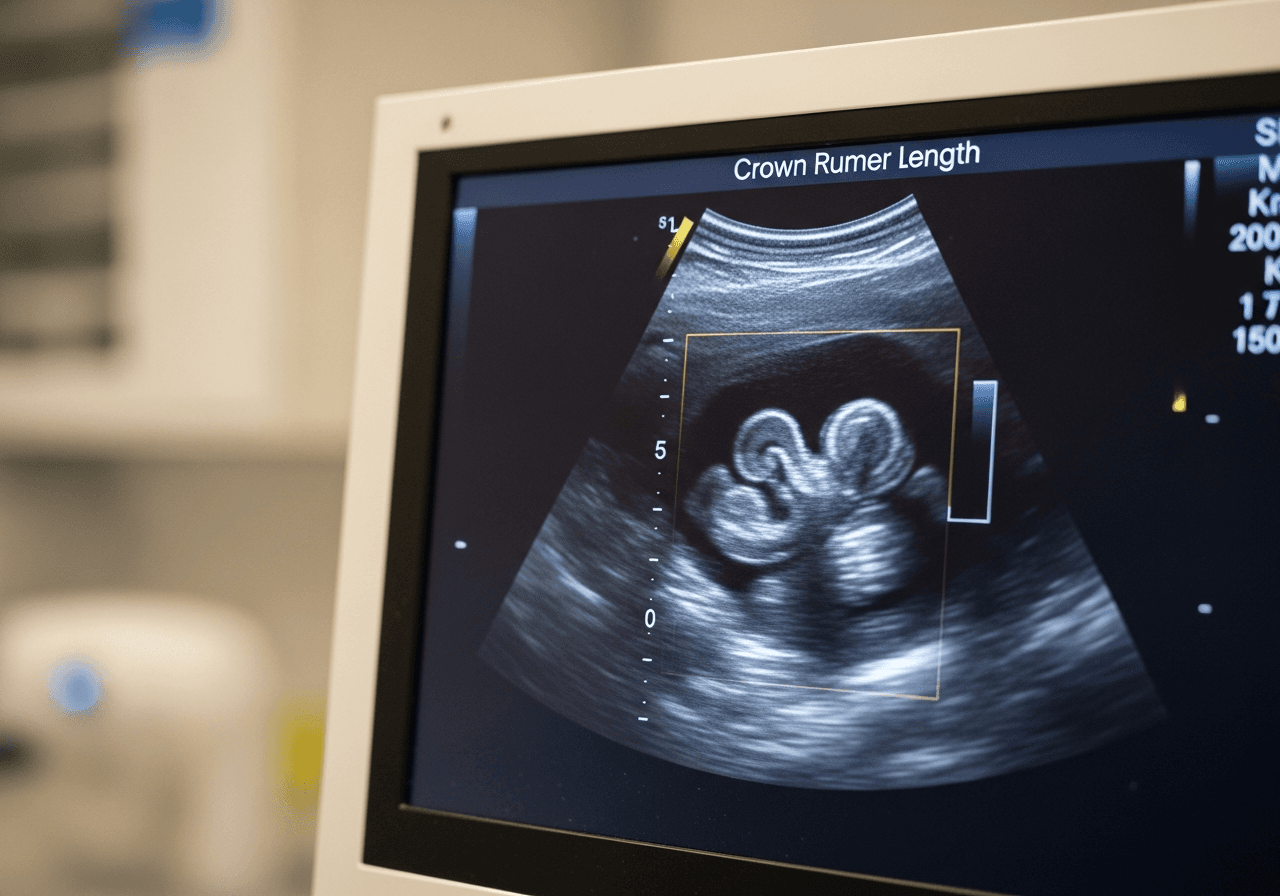

- Détecter une éventuelle grossesse multiple (jumeaux)

- Mesurer la longueur cranio-caudale (LCC)

La mesure de la longueur cranio-caudale (LCC)

La LCC est la mesure de référence à ce stade de la grossesse. Elle correspond à la distance entre le sommet de la tête et le bas des fesses de l'embryon. Cette mesure permet de dater précisément la grossesse avec une marge d'erreur de seulement quelques jours.